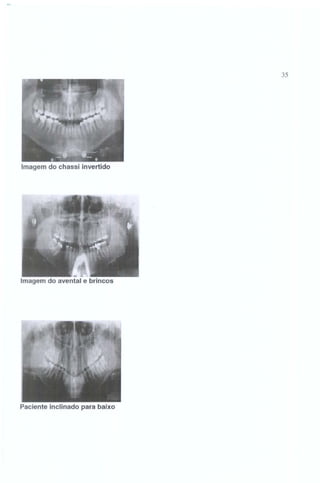

2.5.3 IMAGENS DOS ERROS MAIS COMUNS

Movimentação do paciente no momento da tomada radiográfica

Imagem do avental de ch umbo

35

Imagem do chassi invertido

-

Imagem do avental e brincos

Paciente inclinado para baixo